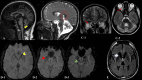

Results: We identified 26 patients (22 families, 15 males) of genetically-confirmed PLAN with a median age of 22.5 years and age at onset of 13.0 years, encompassing various subtypes: infantile neuroaxonal dystrophy (5/26;19.2%), atypical neuroaxonal dystrophy (3/26;11.5%), dystonia-parkinsonism (5/26;19.2%), dystonia-parkinsonism-myoclonus (n = 4, 15.38%), early-onset Parkinson's disease (2/26;7.7%), complex dystonia (2/26;7.7%), and complicated hereditary spastic paraparesis (cHSP; 5/26;19.2%). The common initial symptoms included walking difficulty (7/26;26.9%), developmental regression (6/26;23.1%), and slowness (4/26;15.4%). Dystonia (14/26;53.8%), followed by parkinsonism (11/26; 42.3%), was the most common motor symptom. Non-motor symptoms included cognitive decline (12/26;46.2%) and behavioral changes (6/26;23.1%). Neuroimaging revealed cerebellar atrophy in 23/26 (88.5%) patients and claval hypertrophy in 80% (4/5) of INAD patients. Levodopa responsiveness was noted in 12 of 14 patients with parkinsonism/dystonia who received levodopa, and dyskinesia was noted in 10/11 patients. Genetic analysis revealed a total of 19 unique variants in PLA2G6 gene, of which 11 were novel. Twelve patients harbored the c.2222G>A variant, which is predominantly seen in Asian subpopulations.